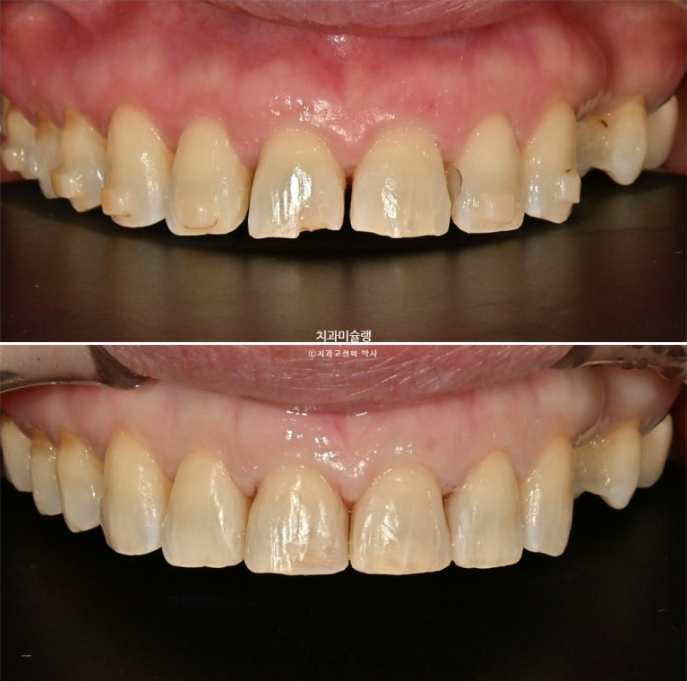

레진치료 직후 모습입니다.

이제 전후 비교해보겠습니다.

24.07~26.01

앞니 각도의 개선이 눈에 띕니다.

아래 앞니는 치간삭제와 함입으로 위 앞니 사이사이 벌어진 공간을 이용하여 뻗친 각도와 골출을 개선하였으며

위 아래 앞니 각각 1.5-2mm 가량 뒤로 들어갔습니다.